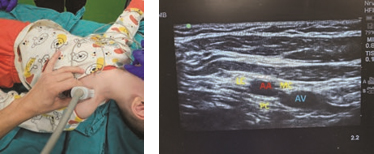

Anatomy and ultrasound characteristics. On this level, anterior and posterior divisions form lateral, medial and posterior cords, named according to their position to the axillary artery. A linear probe is placed in parasagittal plane below the clavicula and medially to the coracoid process (Fig. 5a). Beneath the pectoral muscles lies the axillary artery, which is surrounded by three cords of the brachial plexus; and the axillary vein is poisitioned medial and caudal to the artery (Fig. 5b). The cords of the plexus are visualized as hyperechoic oval structures, but sometimes the medial and posterior cords can be difficult to identify because of their anatomical variations. The in-plane technique is safer, and the needle is advanced from cranial to caudal with target point at 7-8 of the clock level under the axillary artery. At this point, deposition of the local anesthetics encircles the axillary artery in a “U-shape” and provides blocking of all three cords.

Figure. 5. a – position of the linear probe for performing infraclavicular brachial plexus block; b – ultrasound

findings of infraclavicular block in a 3-year-old child: AA – axillary artery, AV – axillary vein, LC – lateral cord, MC – medial cord and PC – posterior cord of the brachial plexus

Clinical tips.

- Place the linear probe medial to the coracoid process and inferior to the clavicle in parasagittal plane

- After identifying the axillary artery, advance the needle toward the posterior cord

- Sometimes, for improved visualization of the cords, abduct the arm to 90°, which brings the cords more superficially and laterally to the axillary artery.